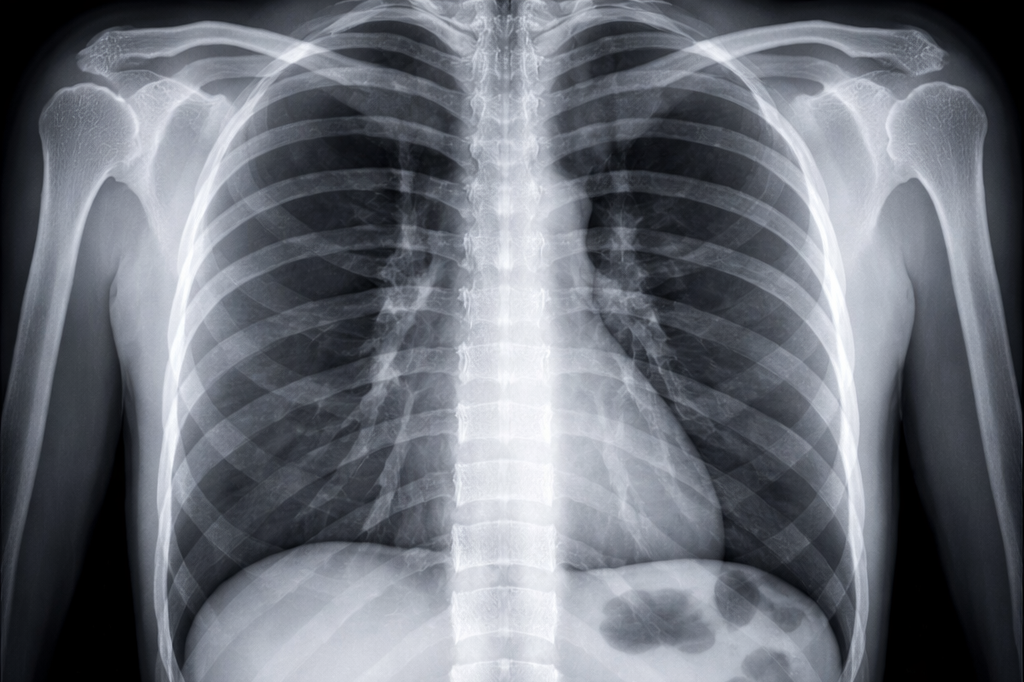

Radiographie standard

La radiographie est un examen d’imagerie utilisant les rayons X pour visualiser principalement les structures osseuses, mais aussi les poumons et certaines parties du thorax.

Elle est fréquemment réalisée pour : le diagnostic de fractures ou de traumatismes, l’exploration des douleurs articulaires ou osseuses, la recherche d’infections pulmonaires (pneumonie), le suivi de pathologies chroniques comme l’arthrose. L’examen est rapide, indolore et ne nécessite généralement aucune préparation particulière.